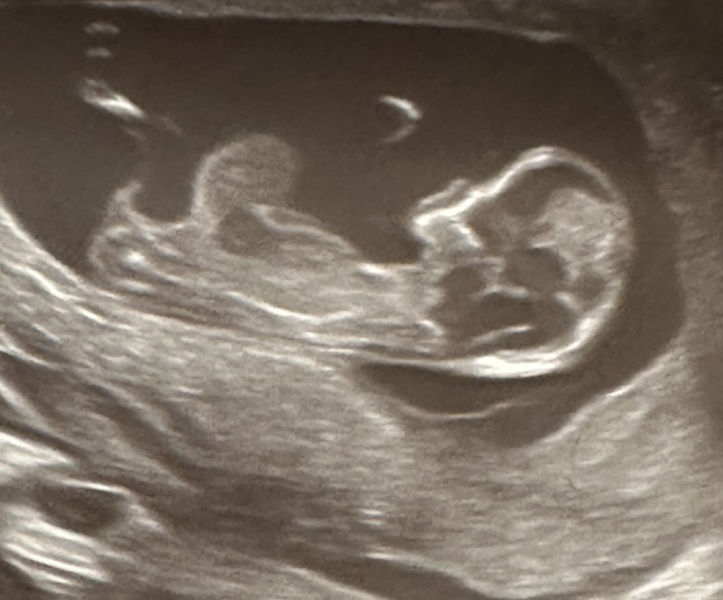

Hello, I am a first time mum to be. I went to have my 12 week baby scan yesterday and the sonographer said there was an abnormality on the baby’s abdomen. I have been referred to Fetal Medicine but in the meantime I am feeling very stressed. Has anyone had a similar experience at their ultrasound? I’ve been reading online and it looks like it could be an omphalocele, but I’m not sure and I’d love to have someone else’s opinion/ previous experience. Thank you!